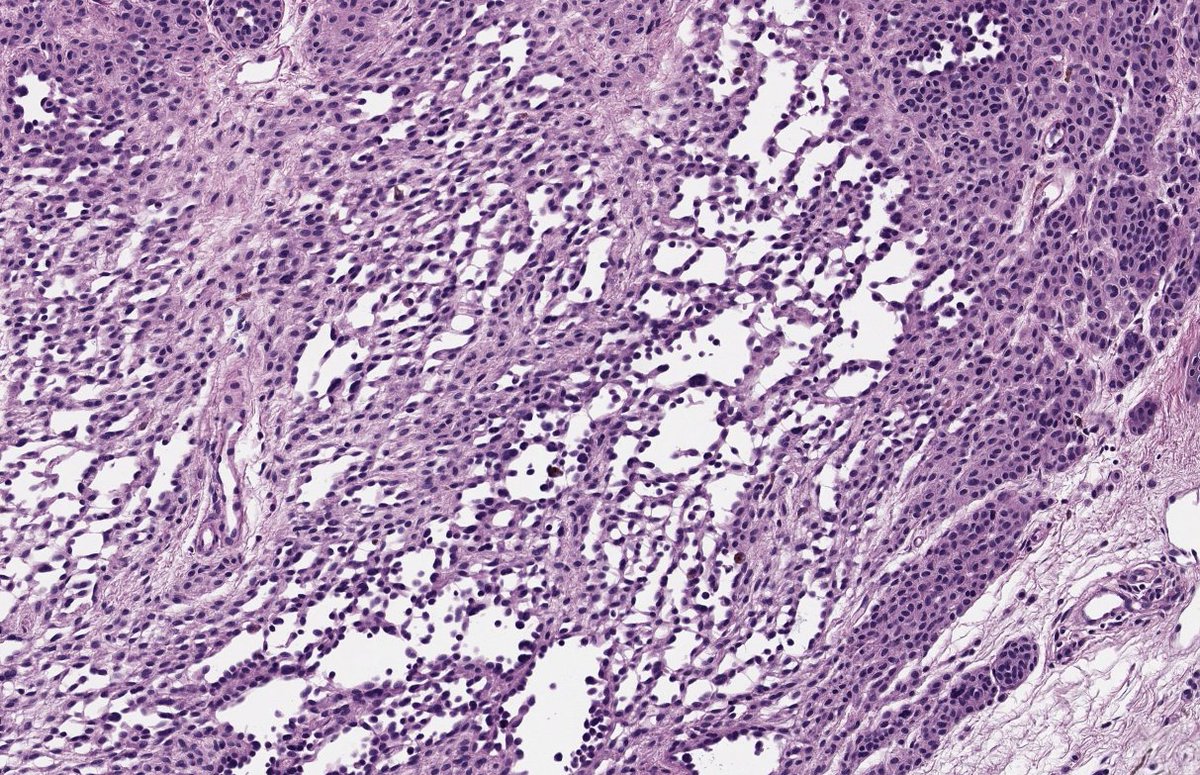

Nice reminder: Periadnexal invasion IS NOT exclusive to melanoma. Skin excision from a 26-year-old man. High-grade dysplastic nevus with adnexal invasion. Great mimic!! #dermpath #PathTwitter #dermtwitter

Nice reminder: Periadnexal invasion IS NOT exclusive to melanoma.

Skin excision from a 26-year-old man.

High-grade dysplastic nevus with  adnexal invasion.

Great mimic!!

#dermpath #PathTwitter #dermtwitter